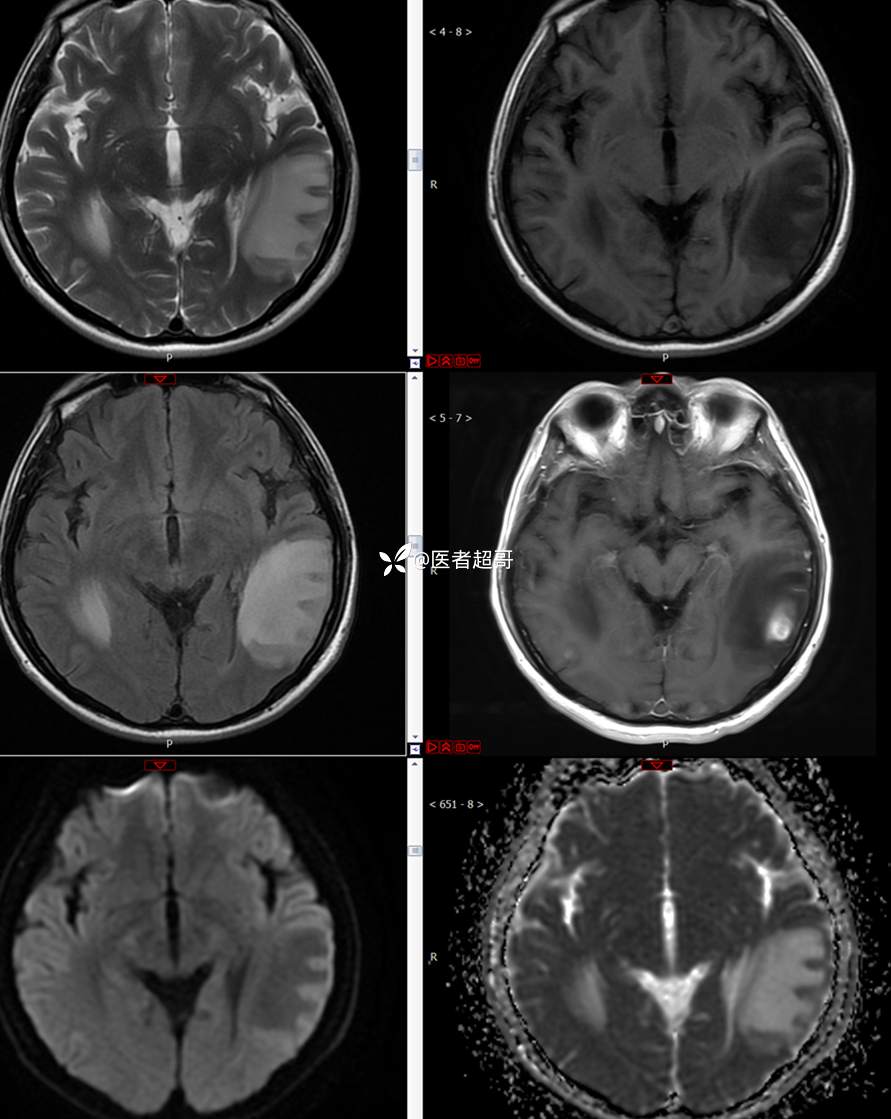

【影诊笔记773】头痛、头晕10天,CT、MRI齐全,请高诊!

主 诉:头痛、头晕10天

现病史:患者10天前无明显诱因感头痛、头晕,伴记忆力减退,无恶心、呕吐,无肢体抽搐及肢体活动不灵等,于我院就诊,行颅脑MR示颅内多发占位,现患者为求进一步治疗于我院就诊,以“颅内占位”收入我科。患者目前神志清,精神可,饮食、睡眠正常,体重无明显变化。

既往史:既往急性肝功能衰竭病史.